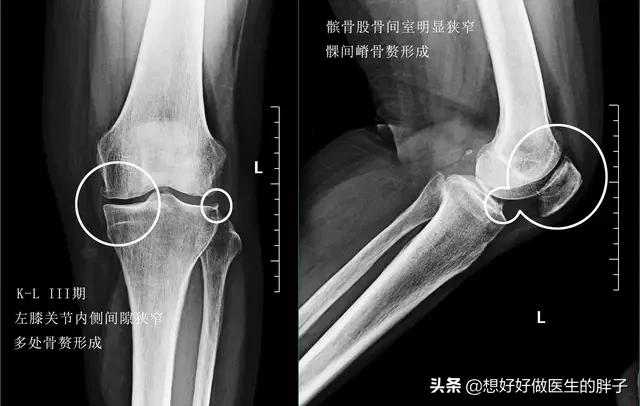

当关节软骨磨损处于中期的时候,患者不仅会在上下楼梯的时候出现疼痛,在走平路的时候也会有明显的关节不适感,而且有的患者在出生的过程中会有明显的响声,有部分患者在这个阶段会出现关节腔内的积液,但是量不会特别大。此时的治疗在坚持康复锻炼为基础的前提下,应该给予关节腔内进行玻璃酸钠注射治疗,帮助增加关节内的软骨弹性,减少关节内软骨的磨损,帮助控制关节的症状;因为此时患者的关节内磨损比较重,在口服氨糖可能并不能帮助患者缓解症状。

到了关节软骨磨损的晚期,很可能关节内负重区的软骨已经被磨得消失殆尽了。所以患者的关节往往会出现明显的间隙狭窄和大量的骨赘形成,此时的患者,严重的关节屈伸角度也会有明显的受限,而且疼痛会对患者的整个生活造成非常大的困扰,有些比较重的患者甚至会出现休息的时候关节也疼痛,而且在夜间休息的时候能疼醒,此时以前的一些治疗方法就很难帮助患者解决问题了,进行关节置换或者是部分关节置换,是解决患者问题的最佳措施(康复锻炼一样要做)。